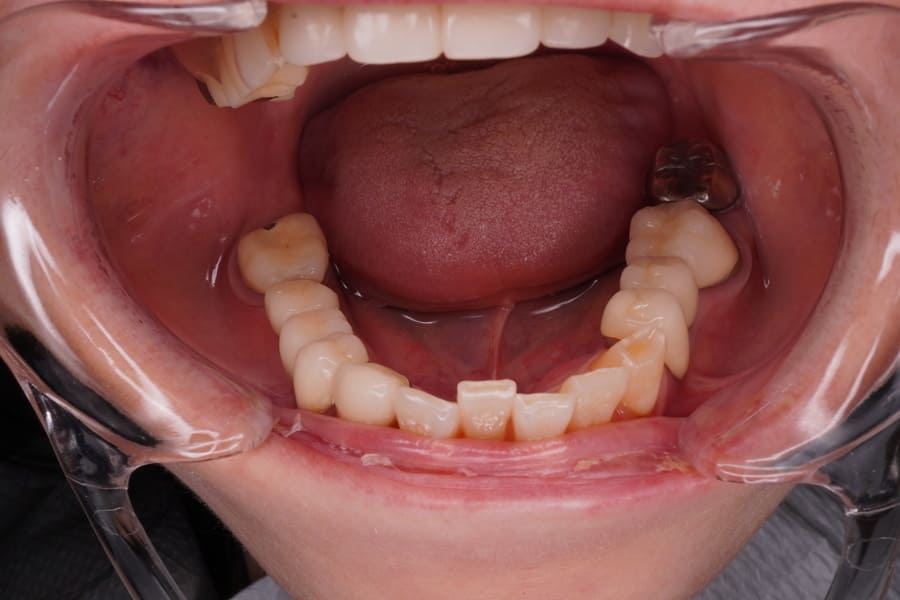

Before

After

主訴 左上のセラミックの歯の歯ぐきが下がって変色した歯が出てきて見た目が気になるのでやり直したい。 性別 女性 年齢 50代 症例概要・補綴専門医としての分析 ・50代女性

・左上5番にオールセラミッククラウンが装着されている。

左上4番にはインプラントによるオールセラミッククラウンが装着されている。

頬側の歯肉退縮が生じており歯頸部に黒変した歯質が露出して審美障害を生じている。

全体的な辺縁不適合が認められた。

セラミック咬合面には若干の咬耗が認められた。

左上5番頬側歯肉辺縁に発赤・腫脹は認められない。

エックス線から歯根に問題は認められなかった。

患者さんには、過度にブラッシングする習慣があり、ブラッシング圧とブラッシング時間のコントロールを指導した。

また、クレンチングの習癖があり、生活指導及びナイトガードの夜間使用をお願いしている。

これらのご指導・お願いが実施されることを前提に、咬合力の強くない女性であること、審美性を重視していることなどからモノリシックジルコニアクラウンではないジルコニアフレームにポーセレンを積層する方法、ジルコボンドクラウンにて再補綴することとした。